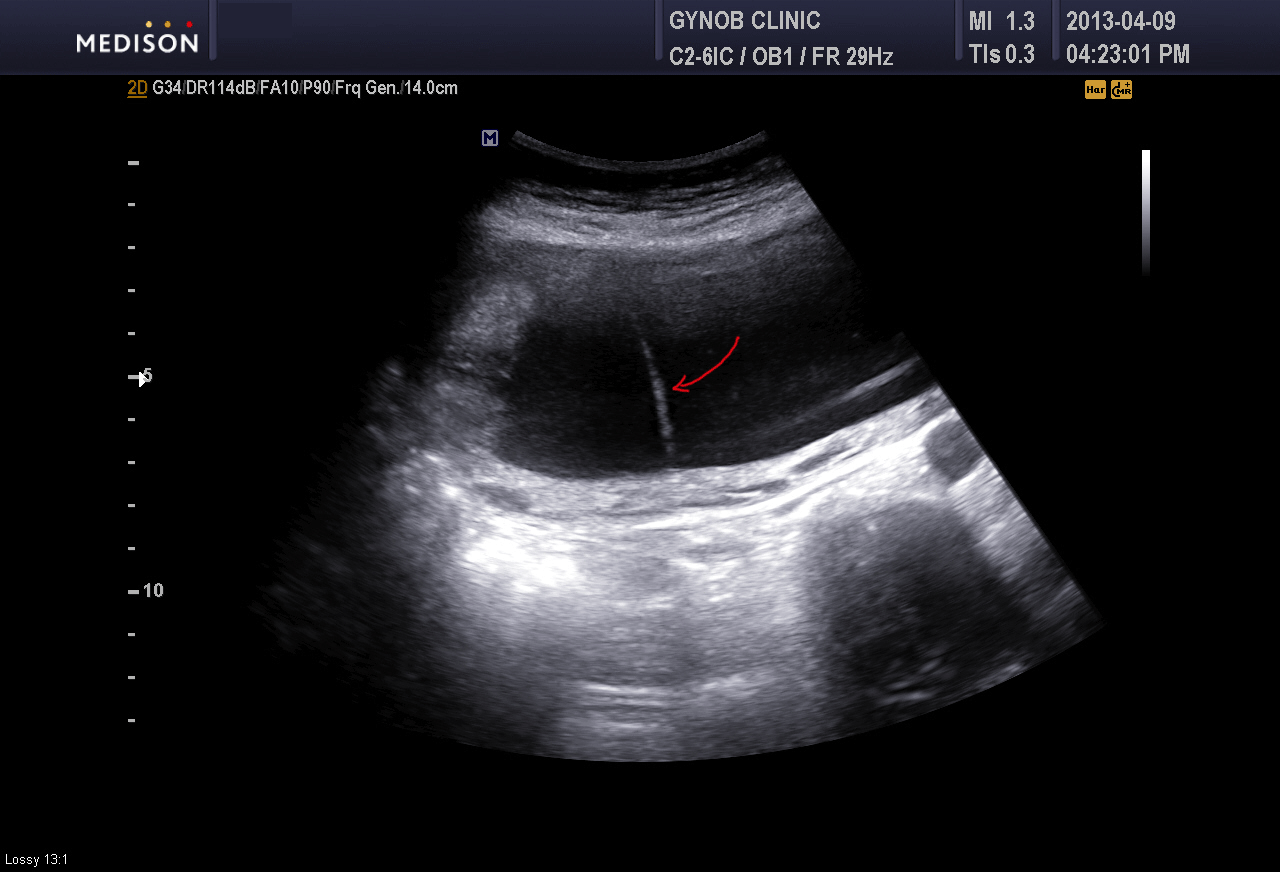

너무 작을 때는 알기 어렵지만 어느 정도 큰 양막대는 초음파 검사를 통하여 쉽게 진단이 될 수 있습니다.

아래 그림은 저희 병원에서 찍은 초음파 사진으로 빨간 화살표로 표시한 부분이 양막대입니다.